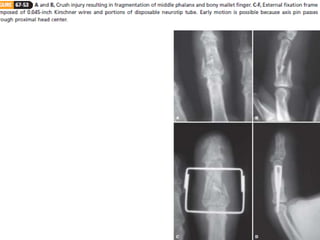

4. Crushing

– Dynamic traction / dorsal spring mechanism.

– The general principle is to establish a foundation at the center

of rotation in the head of P1.

– traction (adjustable or elastic) is applied along the axis of P2

to hold the metaphyseal component of the fracture out to

length

– while allowing early motion to remodel the articular surface